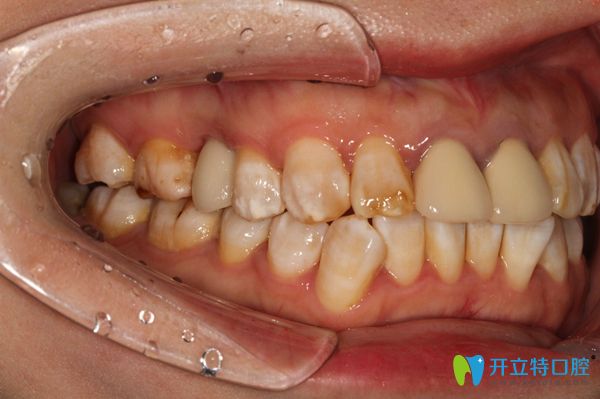

放完種植體之后,醫(yī)生給錢女士戴的是臨時(shí)的牙冠,因?yàn)殄X女士的口腔情況不適合即刻種植,所以,她需要三個(gè)月以后再來(lái)戴真正的牙冠。做完種植牙后,錢女士開(kāi)心的說(shuō):“覺(jué)得自己年輕時(shí)候的那種咀嚼功能,又回來(lái)啦,真舒服”。

在廣州陽(yáng)光樹(shù)口腔戴上牙冠后樣子

▲這是錢女士在廣州陽(yáng)光樹(shù)口腔戴上真正的牙冠后的樣子喲!